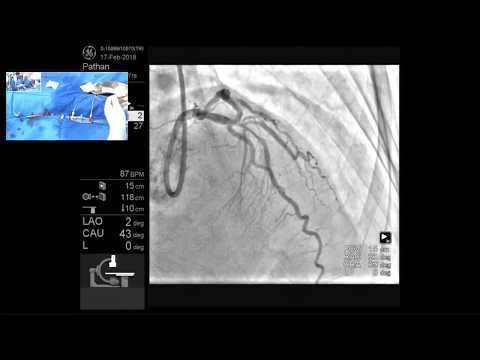

Imaging-Guided (LM) PCI of Prox LAD/D1 Bifurcation